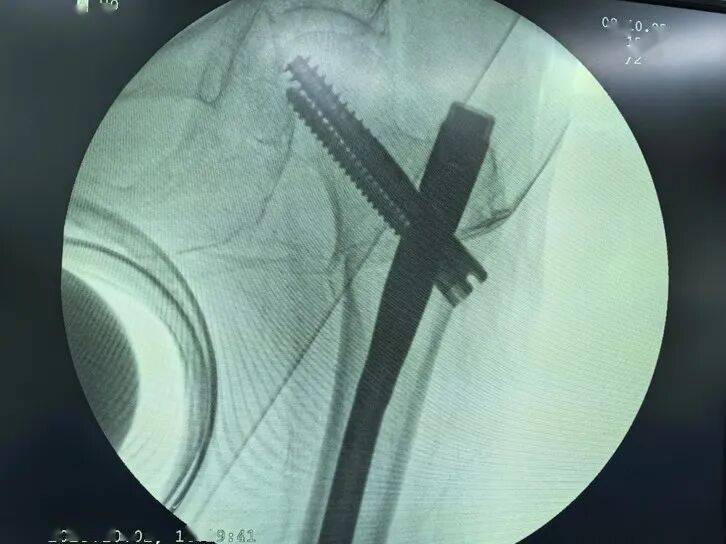

患者术后影像资料

广东省中医院珠海医院急诊科医生为老人迅速完成检查,发现左侧股骨粗隆间骨折,立刻启动老年髋部骨折绿色通道,迅速完善术前检查,并请麻醉科、心内科、ICU等专科会诊和指导治疗,排除手术禁忌症后,在MDT团队检验科、影像科、输血科、超声科等协助下,完成术前准备工作,老人于2日中午被送入手术室并完成手术,此时距离老人受伤还不到24小时。经过5天的良好康复治疗,老人病情稳定,顺利出院。